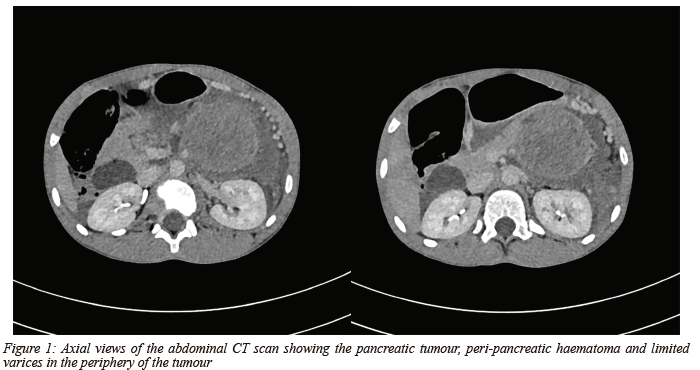

After administering intravenous fluids and analgesia, a CT scan was performed. The scan showed a significant amount of perisplenic free fluid with a heterogeneous soft tissue mass in the tail of the pancreas measuring 64 mm AP x 73 mm TV x 75 mm CC (Figure 1). The mass displaced the bowel and stomach and was associated with a predominantly left retroperitoneal haematoma extending into the pelvis. The splenic artery was displaced superiorly by the mass. Although the splenic vein was poorly visualised numerous coronary collateral vessels could be seen in addition to gastro-oesophageal varices along the greater curvature of the stomach. There was no involvement of the liver, gallbladder, spleen, kidneys, stomach, or small or large bowel.

In our case, there weren't any direct signs of pancreatic injury. The only findings were a heterogenous mass in the tail of the pancreas, together with a retroperitoneal haematoma and free fluid in the pelvis, suggesting underlying pathology as the cause of haemorrhage. Additional findings of gastric and perisplenic varices suggested long-standing pathology.